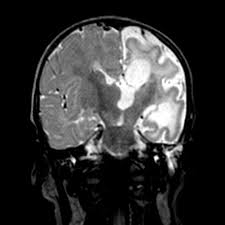

Autoimmune Encephalitis Pathophysiology And Imaging Review Of An Overlooked Diagnosis American Journal Of Neuroradiology

Autoimmune Encephalitis Pathophysiology And Imaging Review Of An Overlooked Diagnosis American Journal Of Neuroradiology from www.ajnr.org

The basal ganglia are usually spared. The differential diagnoses include limbic encephalitis (paraneoplastic), gliomatosis cerebri, and status epilepticus. Limbic encephalitis, mca ischaemia, tumours, effects of seizures) hyperintense t2 signal in the medial temporal lobes, inferior frontal lobes and insula basal ganglia are usually spared Hypertrophic pachymeningitis is a condition where there is localized inflammatory thickening of the dura. This patient went on to have hsv encephalitis proven on csf pcr. Twelve of 27 patients (44%, 95% ci: For a general discussion, and for links to other system specific manifestations, please refer to the article on coccidioidomycosis. Multilocularis, and describes a spectrum of disease involving the spinal cord, the spine, or both.

The changes spare the basal ganglia, a feature which is helpful in distinguishing an mca infarct with hemorrhagic transformation from herpes simplex encephalitis, the diagnosis in this case. Hse may result from primary infection or reactivation from latency, and it frequently involves frontal or temporal lobes, as well as the brain stem. Herpes simplex (hsv) encephalitis is the most common cause of fatal sporadic fulminant necrotizing viral encephalitis and has characteristic imaging findings. It is usually bilateral but asymmetrical. The differential diagnoses include limbic encephalitis (paraneoplastic), gliomatosis cerebri, and status epilepticus. Two subtypes are recognized which differ in demographics, virus, and pattern of involvement. Given the history of fever and seizures coupled with the mri findings of bilateral mesial temporal lobe changes, herpes encephalitis requires clinical consideration. Spinal hydatid disease is an uncommon manifestation of hydatid disease, caused by the larval stage of echinococcus granulosus, or less commonly e. Multilocularis.the larval stage is the cause of hydatid disease in humans 1. The differential diagnoses include limbic encephalitis (paraneoplastic), gliomatosis cerebri, and status epilepticus. Herpes simplex encephalitis (hse) is the most common form of viral sporadic encephalitis and, when left untreated, has a mortality rate of 70% (3, 22). This patient went on to have hsv encephalitis proven on csf pcr. Bilateral temporal lobe t2 hyperintensity refers to hyperintense signal involving the temporal lobes on t2 weighted and flair imaging.